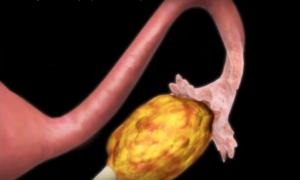

Киста яичника

Если доминантный фолликул продолжает расти, не выпуская яйцеклетку, он порождает фолликулярную кисту. Это доброкачественное образование появляется, если отсутствует овуляция. Причиной такого патологического изменения является гормональный сбой, который чаще всего происходит из-за дисфункции коры головного мозга. На появление фолликулярной кисты также влияют следующие факторы:

Фолликулярная киста способна влиять на регулярность и длительность менструального цикла.

Кистообразное изменение может появиться и на месте образования желтого тела. После лопнувшего фолликула всегда остается жидкость. Если ее количество превышает норму или содержит в себе кровь, на желтом теле появляется киста.

В большинстве случаев такие кистообразные изменения не нуждаются в специальном лечении. Они исчезают самостоятельно через 2-3 цикла, а в случае наступившего зачатия – к началу второго триместра.

Образование фолликулярной кисты

На картинке показана фолликулярная киста левого яичника.

Фолликулярная киста возникает в том случае, если «доминанта» продолжает рост, не выпускает яйцеклетку, соответственно, и овуляция не наступает. Причиной появления доброкачественного образования чаще всего является изменения количества гормонов в женском организме.

Повлиять на появление патологического изменения также могла хирургическая операция, проведенная на органах мочеполовой системы. Наличие фолликулярной кисты влияет на регулярность и длительность менструального цикла.

Киста может образоваться на желтом теле. Это происходит в том случае, если после разрыва фолликула образовалось слишком много жидкости (она образуется всегда, но не в большом количестве) или в ней содержится кровь.

При обнаружении фолликулярной кисты не стоит волноваться — специальное лечение не требуется. Образование исчезает самостоятельно через несколько циклов, а если наступила беременность — после первого триместра.

- Образование кист. Доминантный фолликул не лопается, переполняется жидкостью и растягивается, формируя доброкачественное образование – кисту (она может расти или самостоятельно регрессировать, то есть лопнуть и исчезнуть).